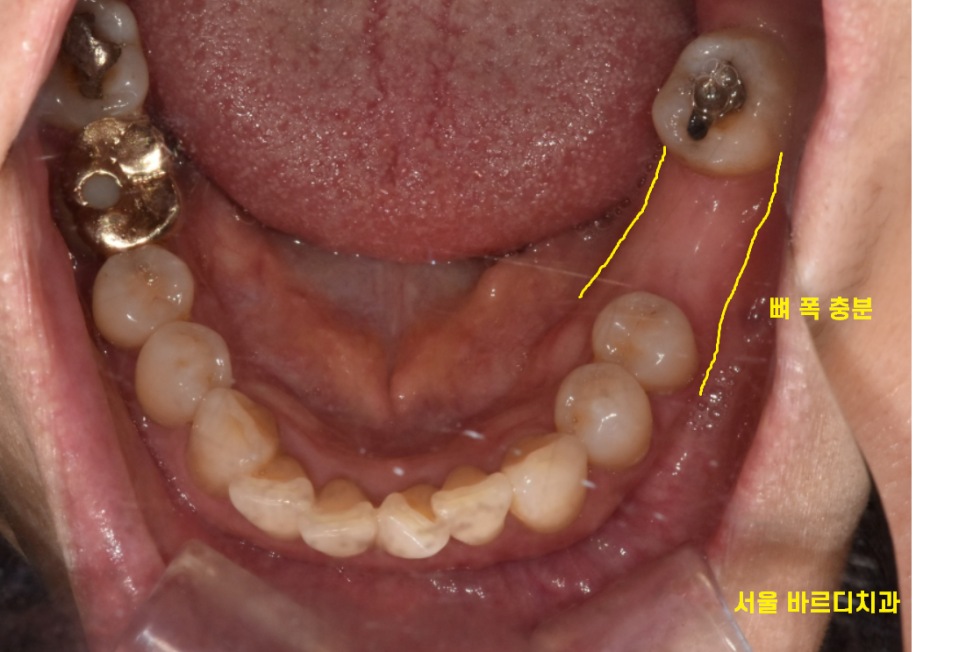

제일 정확한 것은 직접 보아야겠죠?

이어진 입 안 검사

환자분 입안을 보았을 때

뼈 폭도 충분해 보였습니다.

아래 어금니 임플란트 1개라

더 기다리지 않고

그냥 심어도 될 수준이었습니다.